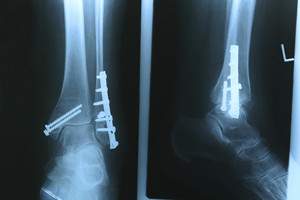

Possible Treatment of a Broken Foot

A common reason a broken foot may occur can be from falling off of a ladder, or it may become injured from participating in sporting events. The bones that are located between the toes and the ankle are referred to as the metatarsals. They can be prone to stress fractures, which typically happen from overuse. The average healing time for a broken foot is generally six to twelve weeks. Many daily activities are able to be completed as the healing process occurs when a walking boot or cast is worn. For more severe fractures, it may take longer if surgery is required. If you have pain in your feet as a result of either a fall or something else, it is advised that you consult with a podiatrist.

A broken foot requires immediate medical attention and treatment. If you need your feet checked, contact Roy Moeller, DPM from Foot & Ankle Physicians West. Our doctors can provide the care you need to keep you pain-free and on your feet.

Broken Foot Causes, Symptoms, and Treatment

A broken foot is caused by one of the bones in the foot typically breaking when bended, crushed, or stretched beyond its natural capabilities. Usually the location of the fracture indicates how the break occurred, whether it was through an object, fall, or any other type of injury.

Those that suspect they have a broken foot shoot seek urgent medical attention where a medical professional could diagnose the severity.

Treatment for broken bones varies depending on the cause, severity and location. Some will require the use of splints, casts or crutches while others could even involve surgery to repair the broken bones. Personal care includes the use of ice and keeping the foot stabilized and elevated.